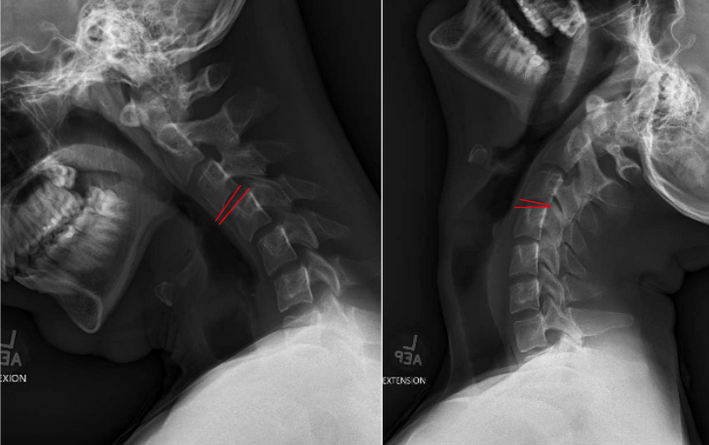

Cervical Flexion-Extension

Cervical angulation, also referred to as segmental rotation, measures the change in angular alignment between two adjacent vertebrae when the neck moves from full flexion to full extension.

The measurement focuses on the angular difference between vertebral endplates at each functional motion segment.

This is measuring total range of motion at each segment, which is distinct from the White-Panjabi criterion for angular discontinuity between adjacent segments.

• Draw Measurement Lines

For each segment on flexion and extension films:

• Draw a straight line along the inferior endplate of the superior vertebra (e.g., C4).

• Draw a straight line along the superior endplate of the adjacent inferior vertebra (e.g., C5).

• Measure the Angle in Each Position

• Use PACS angle tools to measure the intervertebral angle in flexion and extension.

• Angles typically open posteriorly in extension and anteriorly in flexion.

• Calculate Segmental Angulation

• Angulation = |Angle in Flexion − Angle in Extension|